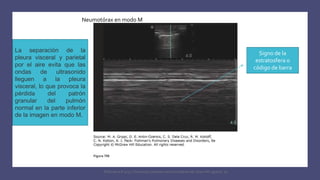

Signo de la

estratosfera o

código de barra

Neumotórax en modo M

La separación de la

pleura visceral y parietal

por el aire evita que las

ondas de ultrasonido

lleguen a la pleura

visceral, lo que provoca la

pérdida del patrón

granular del pulmón

normal en la parte inferior

de la imagen en modo M.

El patrón de modo M del

neumotórax a menudo se

denomina signo de “estratosfera”

o “código de barras”